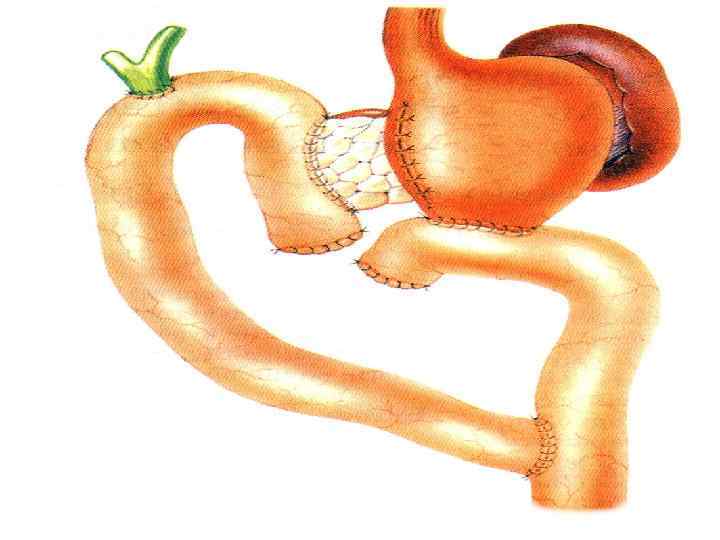

Этапы стандартной ГПДР • • • 1. Мобилизация 12 -перстной кишки 2. Выделение трубчатых структур гепато-дуоденальной связки 3. Выделение верхней брыжеечной вены 4. Мобилизация и отсечение дистальной части холедоха 5. Мобилизация и пересечение начальной части тощей кишки 6. Пересечение гепатикохоледоха после мобилизации желчного пузыря • 7. Пересечение поджелудочной железы по перешейку • 8. Пересечение связок крючковидного отростка, удаление комплекса • 9. Реконструктивный этап